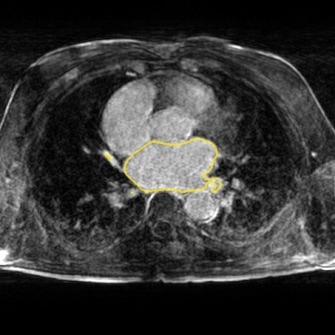

We show the results of our evaluation in Table 1, and a sample reconstruction in Figure 2. RecNet performed best in terms of PSNR, which is expected as its training objective directly corresponds to this metric, but its reconstructions were over-smoothed. DLMRI had the lowest MOS, with its reconstructions showing heavy oil paint artifacts. DAGAN, combining MSE loss with a visual loss function without any further precautions, suffered from low PSNR. While its reconstructions also looked sharp, they were noisy and often displayed aliasing artifacts, which was reflected in a lower MOS compared to our method. Our proposed approach achieved significantly444Significance determined by a two-sided paired Wilcoxon signed-rank test at . higher mean opinion score than all other methods, while still maintaining high PSNR. Reconstructions obtained by our method appeared sharper with better contrast. Moreover, our method achieved the highest SIS close to segmentation performance on the ground truth data, which indicated that the segmented objects were clearly visible in the reconstructed images.

The following images show more samples for 8-fold undersampling. For each of the seven patients of the test set, a random slice showing the left atrium was selected. The contour of the predicted segmentation of left atrium is shown in yellow, the contour of the ground truth segmentation in red.